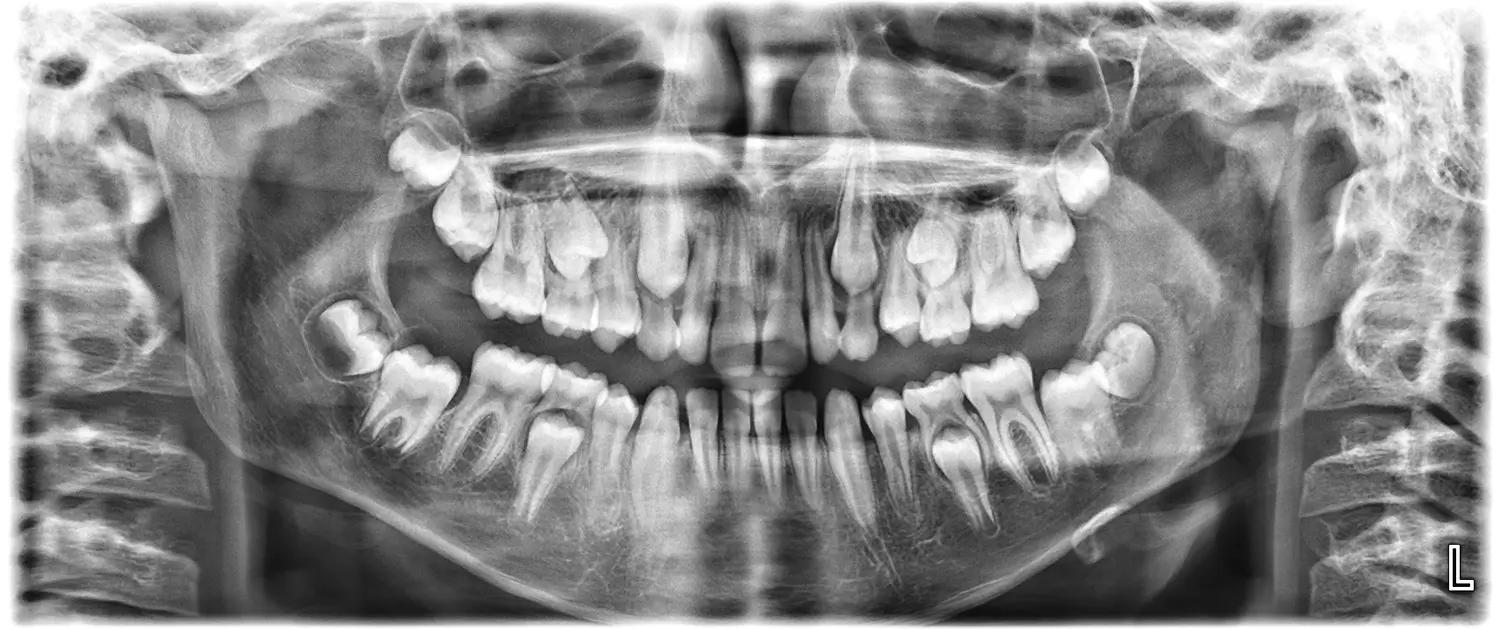

По време на профилактичните прегледи, ние ще следим и ще Ви информираме дали Вашето дете има нужда от ортодонтски преглед. Проследяването на пробива на млечните и постоянните зъби ни позволява да установим навреме отклонения в подреждането, липса на място, задържани зъби или неправилна захапка. Ранната диагностика дава възможност за по-лесна и щадяща корекция и често предотвратява по-сериозно ортодонтско лечение в бъдеще.

Първата консултация с ортодонт е препоръчителна около 6–7-годишна възраст, когато започва смяната на зъбите. Дори да няма видим проблем, ранният преглед позволява да се оцени развитието на челюстите и захапката. При нужда може да се предприеме ранно лечение, което да улесни или съкрати бъдещата терапия.